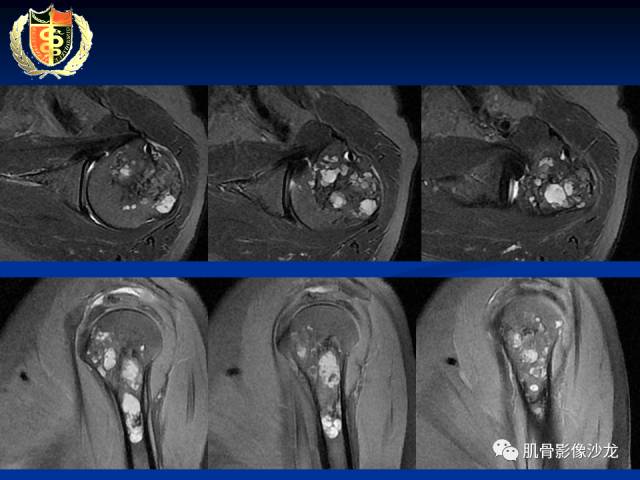

何春祥 20:28

内生软骨瘤?

葛英霖 20:28

有症状,有骨膜反应,还是考虑肉瘤比较合适

软骨肉瘤?

目前看考虑软骨来源是合理的

这些应该是钙化吧

骨膜反应是连续的

里面的高信号是软骨吧